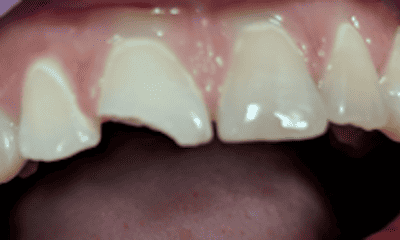

Fractured tooth fixed with a tooth colored composite filling.